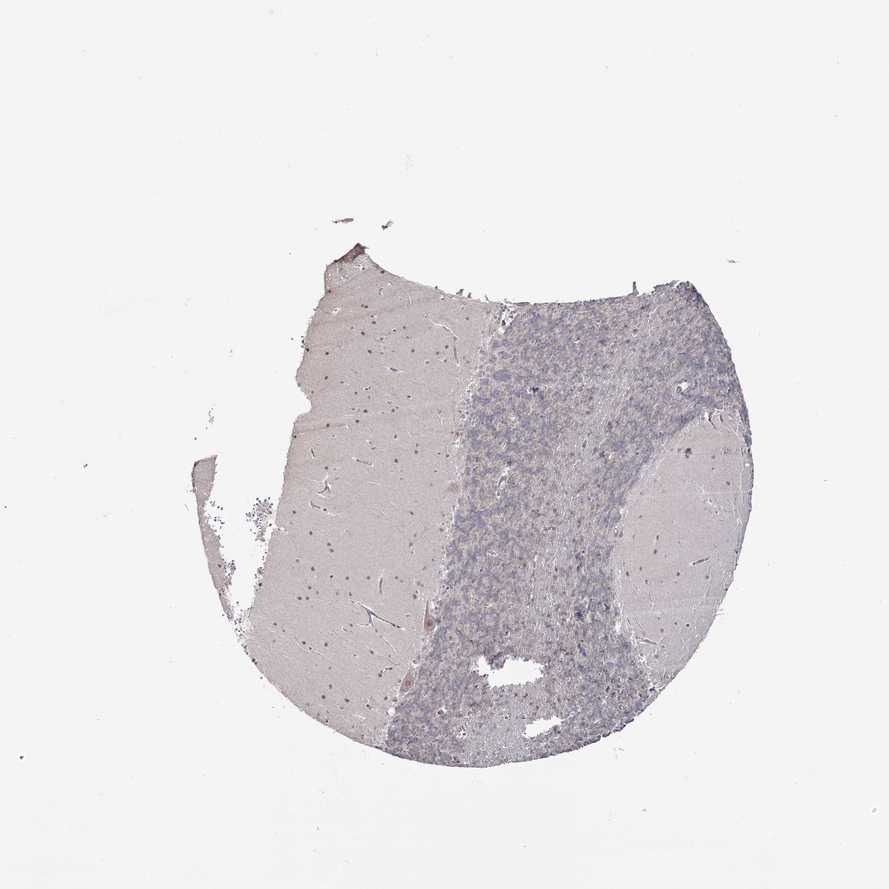

BRAIN CEREBELLUM Show tissue menu

CEREBELLUM - Expression summary

CEREBELLUM - Antibody stainingi

Antibody staining in the annotated cell types in the current human tissue is reported as not detected, low, medium, or high, based on conventional immunohistochemistry profiling in selected tissues. This score is based on the combination of the staining intensity and fraction of stained cells.

Each image is clickable and will lead to virtual microscopy that enables deeper exploration of all samples and also displays staining intensity scores, fraction scores and subcellular localization as well as patient and tissue information for each sample.

Antibody HPA038225Antibody HPA038614

Purkinje cells MediumMedium

Cells in granular layer Not detectedLow

Cells in molecular layer MediumMedium